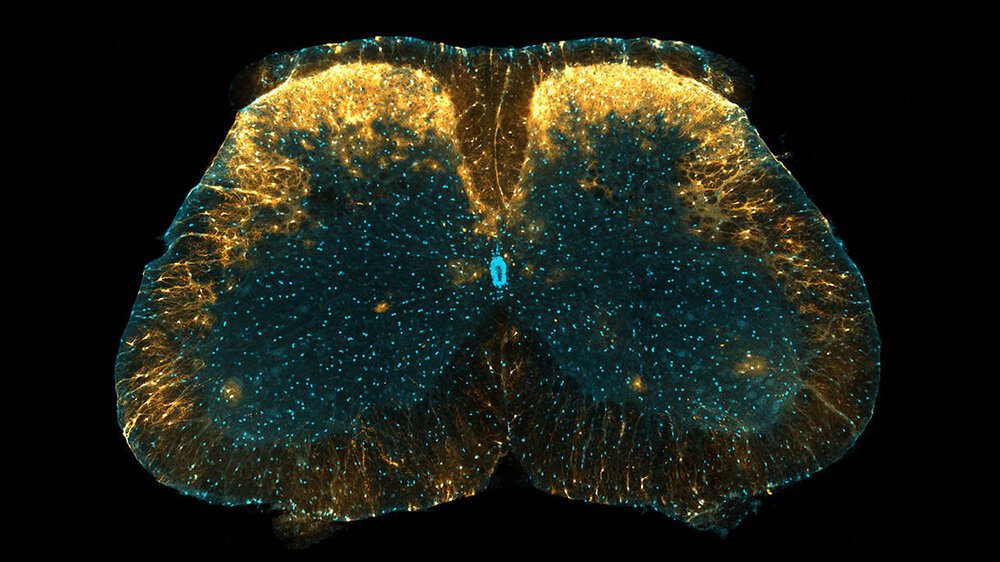

در میان انواع مختلف سلولهای گلیا ، آستروسیتها بیشتر در سیستم عصبی مرکزی دیده می شوند ، اما بر خلاف نورونها در قسمتهای مختلف مغز ، محققان هنوز نتوانسته اند درک درستی از طبقه بندی آستروسیتها که دارای ویژگیهای مشخص هستند ، بدست آورند.

این تیم به سرپرستی محقق دانشگاه کیوتو ، ماکوتو تسودا ، گروه منحصر به فردی از آستروسیت های ستون فقرات را کشف کردند که نقش مهمی در تولید حساسیت به درد دارند.

این گروه از آستروسیت ها که در دو لایه خارجی ماده خاکستری مغز نزدیک پشت نخاع وجود دارد ، در مناطقی قرار دارند که اطلاعات حسی عمومی مانند فشار ، درد و گرما را از بدن به مغز منتقل می کنند.